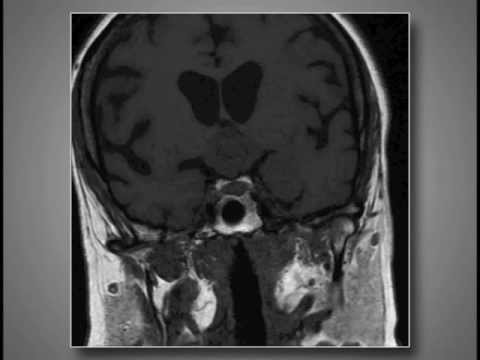

Hellow guys, Welcome to my website, and you are watching Transchoroidal Fissure Approach for Resection of Third Ventricle Cavernoma. and this vIdeo is uploaded by NEUROSURGERY Journal at 2018-02-01T13:11:16-08:00. We are pramote this video only for entertainment and educational perpose only. So, I hop you like our website.